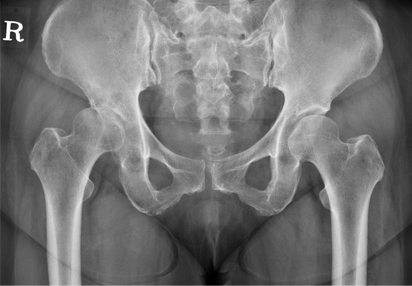

우리나라에서 비교적 흔한 질환인 대퇴 골두 무혈성 괴사증에 대해서도 괴사부위가 일부에 국한되어 있는 경우, 괴사되지 않은 건강한 부위를 하중을 받는 부위로 이동시켜서 병의 진행을 완화시킬 목적으로 절골술을 시행하기도 합니다. 대퇴골 절골술 후 확실한 고정이 필수적이므로 적절한 금속판을 사용하여 고정해야 합니다.

고관절 주위 절골술 이미지